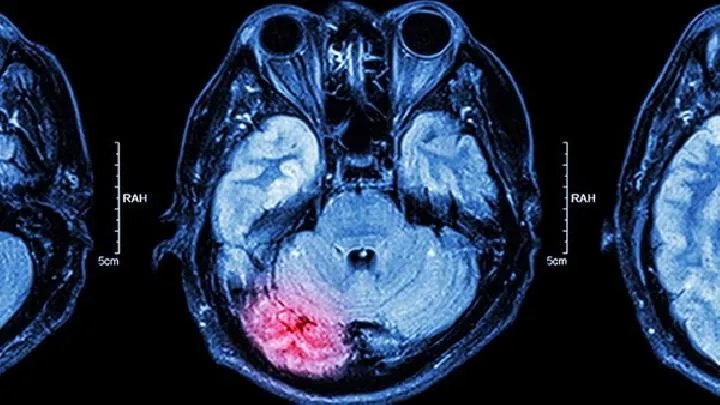

的有关信息介绍如下:无脑是一种神经管畸形。科学研究证明,神经管畸形的发生是由于胚胎期间遗传和环境因素的影响,导致神经管闭合不全,导致无脑畸形和脊柱裂纹。环境因素直接或间接作用于胚胎,特别是在胚胎期的第三和第四周,对神经系统有很大的影响,容易导致畸形。

医学研究已知通过孕妇胎盘屏障进入胎儿的化学物质600它们可能导致受精卵无法植入,胚胎发育迟缓,或染色体突变或基因突变,可能导致流产和死产,更多的是导致胚胎发育不全。虽然精神和情感因素对孕妇和胎儿有影响,但它们并不直接作用于胚胎神经系统的发育,也不是无脑畸形儿童的直接原因。因此,孕妇的情绪波动,或在怀孕期间与他人争吵,不会产生无脑畸形的儿童。“看猴子耍把戏”、“看人盖新房”没有科学依据。中国是胎儿神经管畸形发病率高的国家,每年都发生在世界各地40在万例中,中国占有1/4,高达10一万例。中国妇幼保健中心通过对中国北方山西、河北、南方江苏、浙江等地孕妇为期一年的观察研究,表明妊娠早期叶酸缺乏是神经管畸形的主要原因之一。有神经管畸形家族史的家庭或夫妇,有不明原因流产、早产、死产、死产的家庭或夫妇,有致畸或放射性物质接触史的夫妇,已确定或可能成为遗传疾病致病基因的携带者,神经管畸形的风险也。妊娠早期感冒、发烧妇女不会引起胎儿脊柱裂或无脑畸形。一般来说,感冒不发烧,或只有轻度发烧,伴有细菌感染,病情加重可能会出现高烧现象。发烧有影响,尤其是在怀孕期间13~26天气有高热史,容易出现脊柱裂或无脑畸形。因此,在怀孕早期有发热史的孕妇应在分娩前进行B为了明确诊断,超检。妊娠早期接触放射线的妇女通常在妊娠早期接触辐射检查,不会引起胎儿神经管畸形。但大剂量辐射会对胚胎发育产生不良影响,可导致胚胎死亡或各种类型的出生缺陷,包括无脑畸形。胎盘在不同的发育阶段有不同的不同的感觉,怀孕后是第一个18~20天接受X线照射会导致孕卵死亡。怀孕后的第一个20~50天,如果剂量较大,会造成严重畸形;怀孕后50虽然不诱发畸形,但也会使胎儿发育迟缓。早孕应避免X照射腹部。怀孕早期服用一些药物,孕妇早期服用,一般不会引起胎儿神经管畸形,但如果服用大量抗肿瘤药物(氨甲喋喋不休的硫基嘌呤)、激素药物(如强松)、抗惊厥药物(苯妥英钠)等,可能导致胎儿脊柱裂纹和无脑畸形。